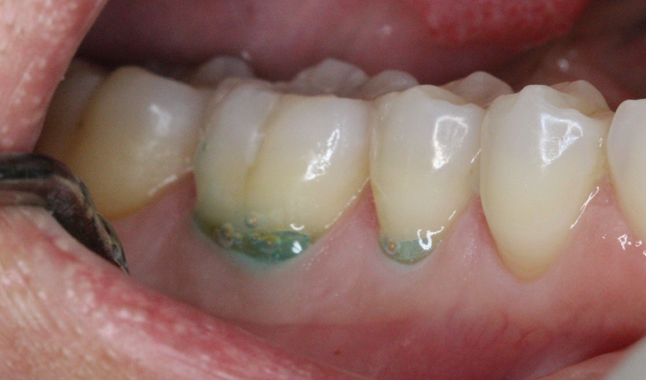

Selective-etch for direct resin restoration.

At our initial restorative visit, the plan was to begin on the left side, which included the crown preparation. After preparation of the teeth, we opted to restore the direct restoration. There was some concern for the depth of the restoration, so we chose a selective-etch approach.

By etching only the enamel and superficial dentin, we were able to achieve the micro mechanical retention in those areas, while eliminating the risk of sensitivity from the over etching of dentin.